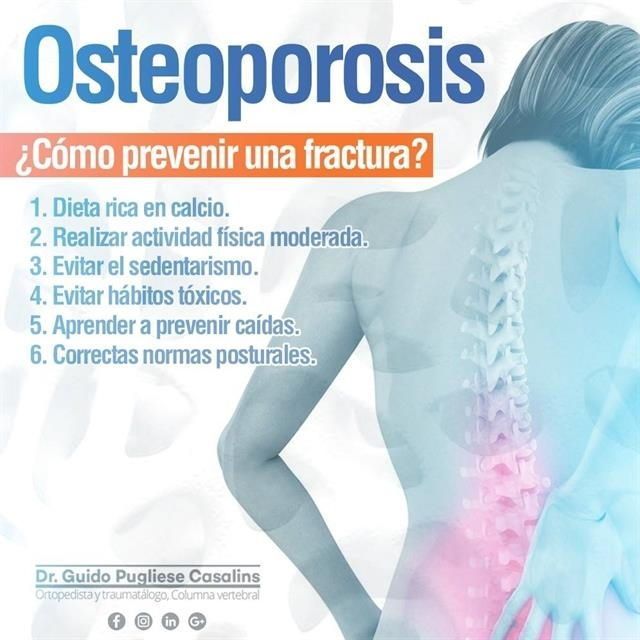

Ortopedista y traumatólogoOrtopedista de columna vertebralEscoliosis

Las especialidades de Dr. Guido Pugliese Casalins son: Ortopedista y traumatólogo, Ortopedista de columna vertebral, Escoliosis.